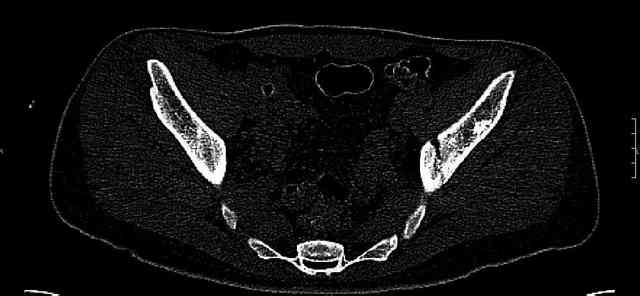

Re: Нелеченный перелом вертлужной впадины

Some more images. Does it help to guess which part of the acetabulum is displaced?